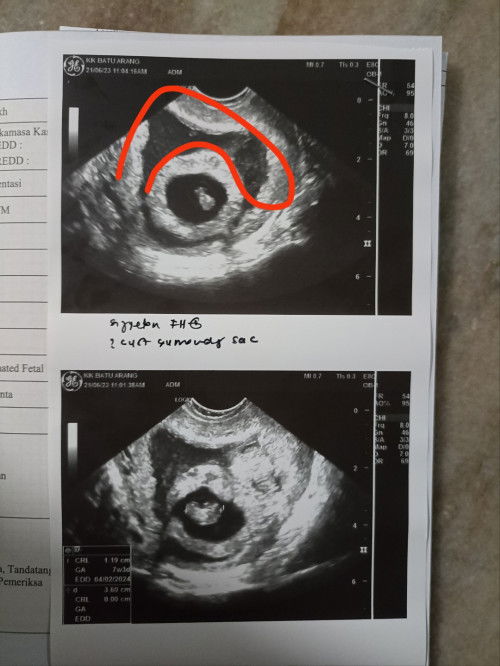

Scan kandungan 7w

Assalammualaikum semua.. nak tanya la... Adakah kemungkinan yg saya bulatkan tu cyst atau fibroid ? Sebab td saya scan doc takut ada cyst ,saya ada history gugur 2 kli, gugur hr tu pun xde cuci... Dia keluar habis.. ada sesiapa tahu x atau sesiapa yg pernah mengalami??? Sbb doc scan biasa x nampak tp bila scan dr tvs baru nampak yg saya bulatkan tu.. Tp doc kata lg 2 mnggu scan blk utk tgk mcm mana.. incase ada lg,kena rujuk o&g pula. Harap2 tiada apa2lah... Risau pula saya😔